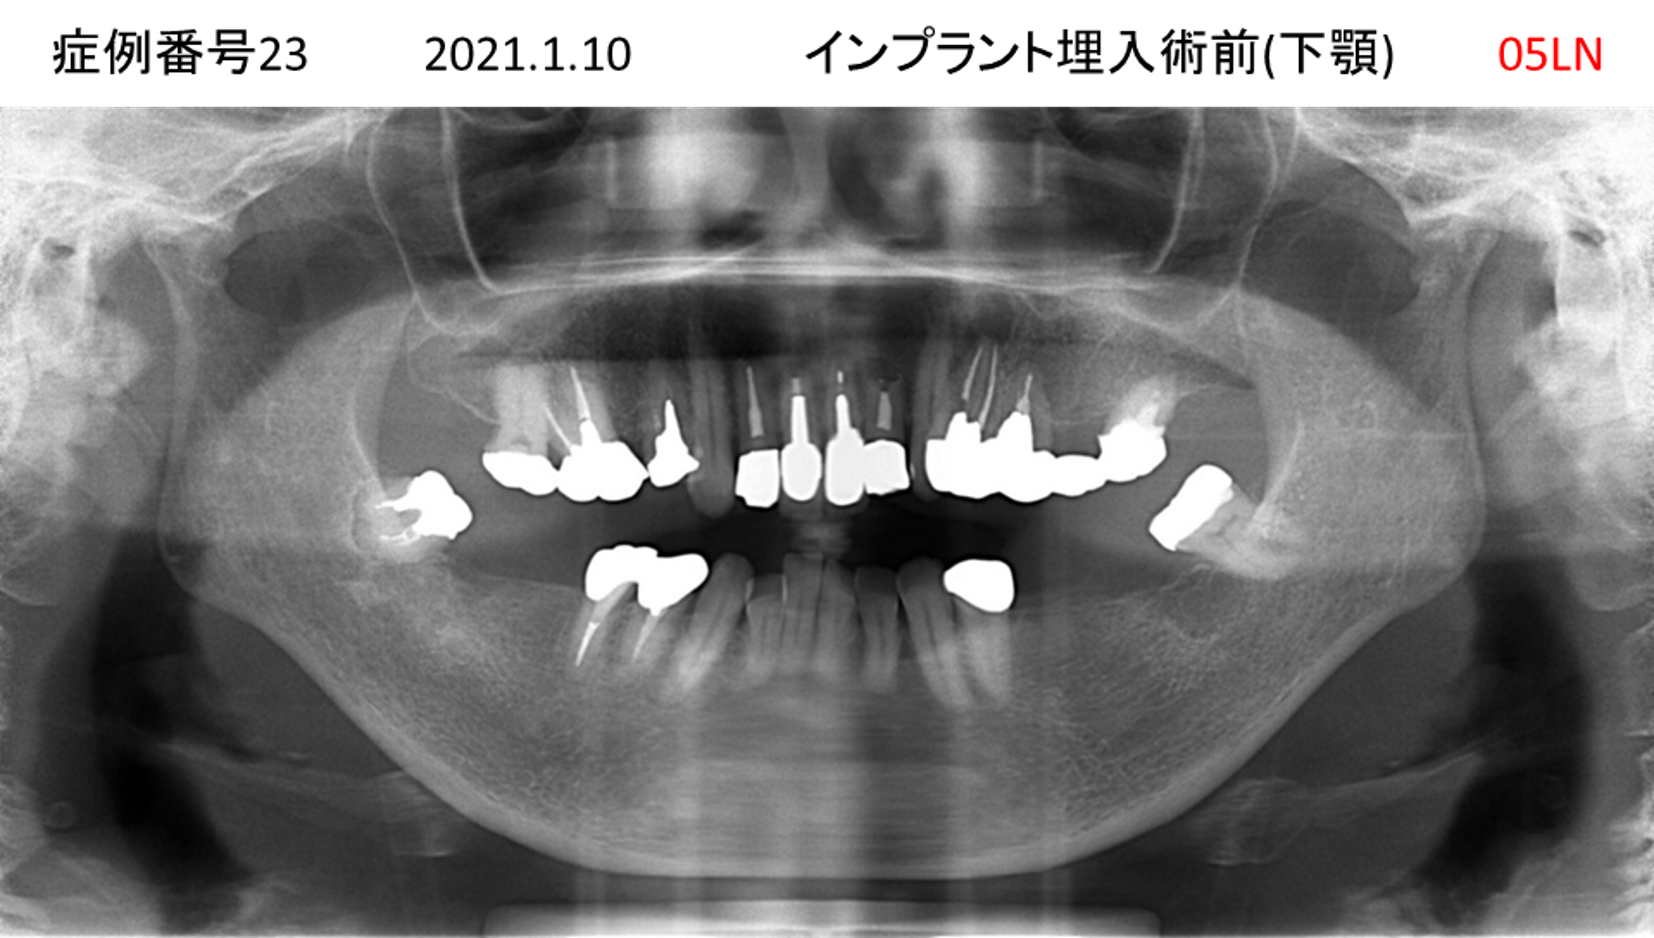

奥歯で噛めない患者様のインプラント症例

| 治療名称 |

インプラント |

| 治療費用 |

365万円+税 |

| 治療期間 |

5か月 |

| 患者さんの症状(主訴) |

奥歯で噛めない。上の前歯が揺れてきた。 |

| 治療内容 |

抜歯即時インプラント |

| 治療結果 |

食事に困らない。見た目がとても良くなった。 |

| 治療の注意点(リスク/副作用) |

インプラントが壊れたら再治療が必要 |